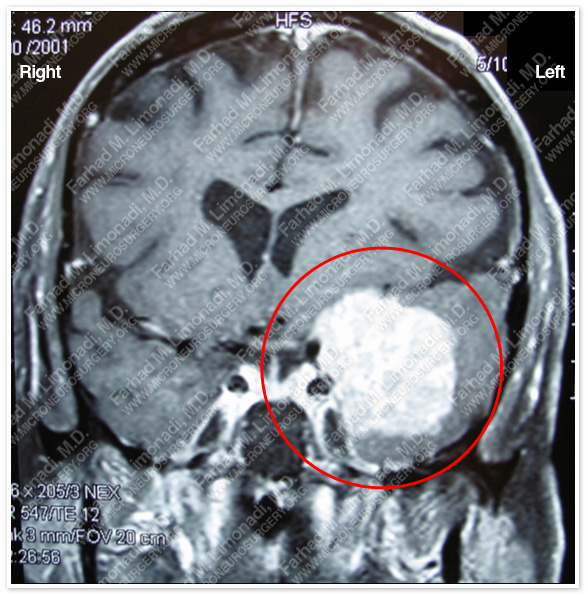

Imaging

MRI scan of the patient’s brain shows a left extraaxial tumor at the sphenoid wing extending in the frontal and temporal lobe region.